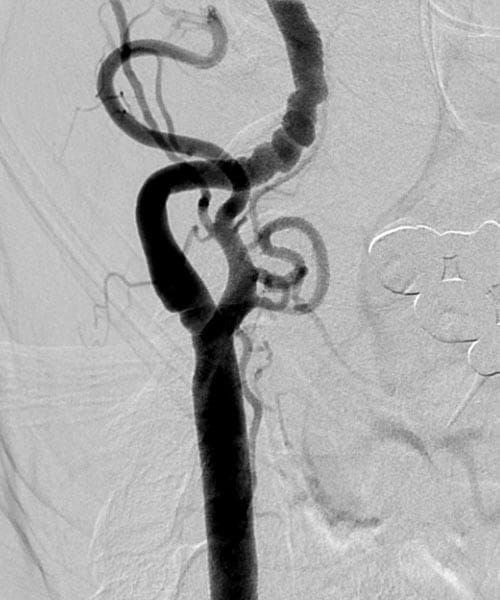

UH vascular specialists diagnose FMD through a variety of vascular imaging tests. Learn more about the ways we diagnose FMD.

Microscopic view of FMD